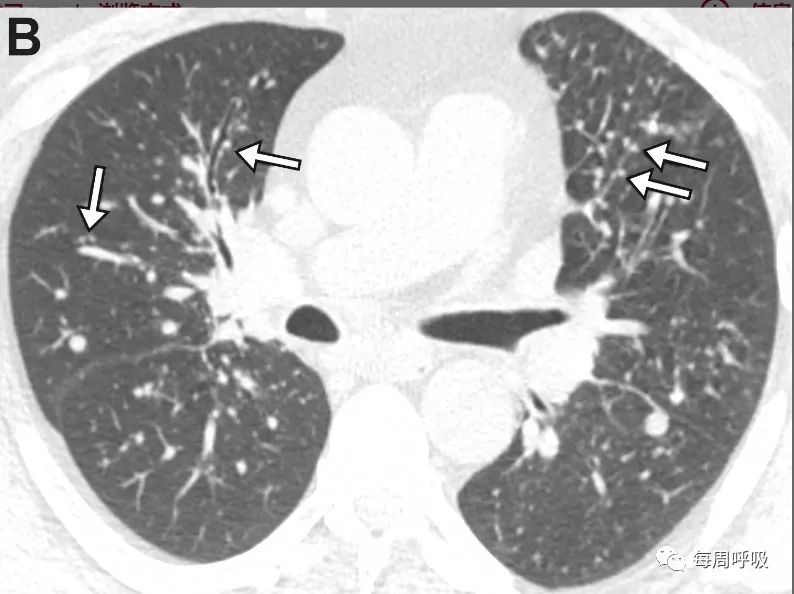

33ea0028f1b2dd034b3d78061d6054bb.jpg

图 5. 42 岁溃疡性结肠炎女性患者 6-巯基嘌呤诱导的 MIPI,她在开始 6-巯基嘌呤治疗后出现呼吸急促。横断面 (B) CT 图像显示 MIPI 的小叶中心 GGN 模式,有许多细微的小叶中心 GGN(B 中的箭头),胸膜下不受影响。